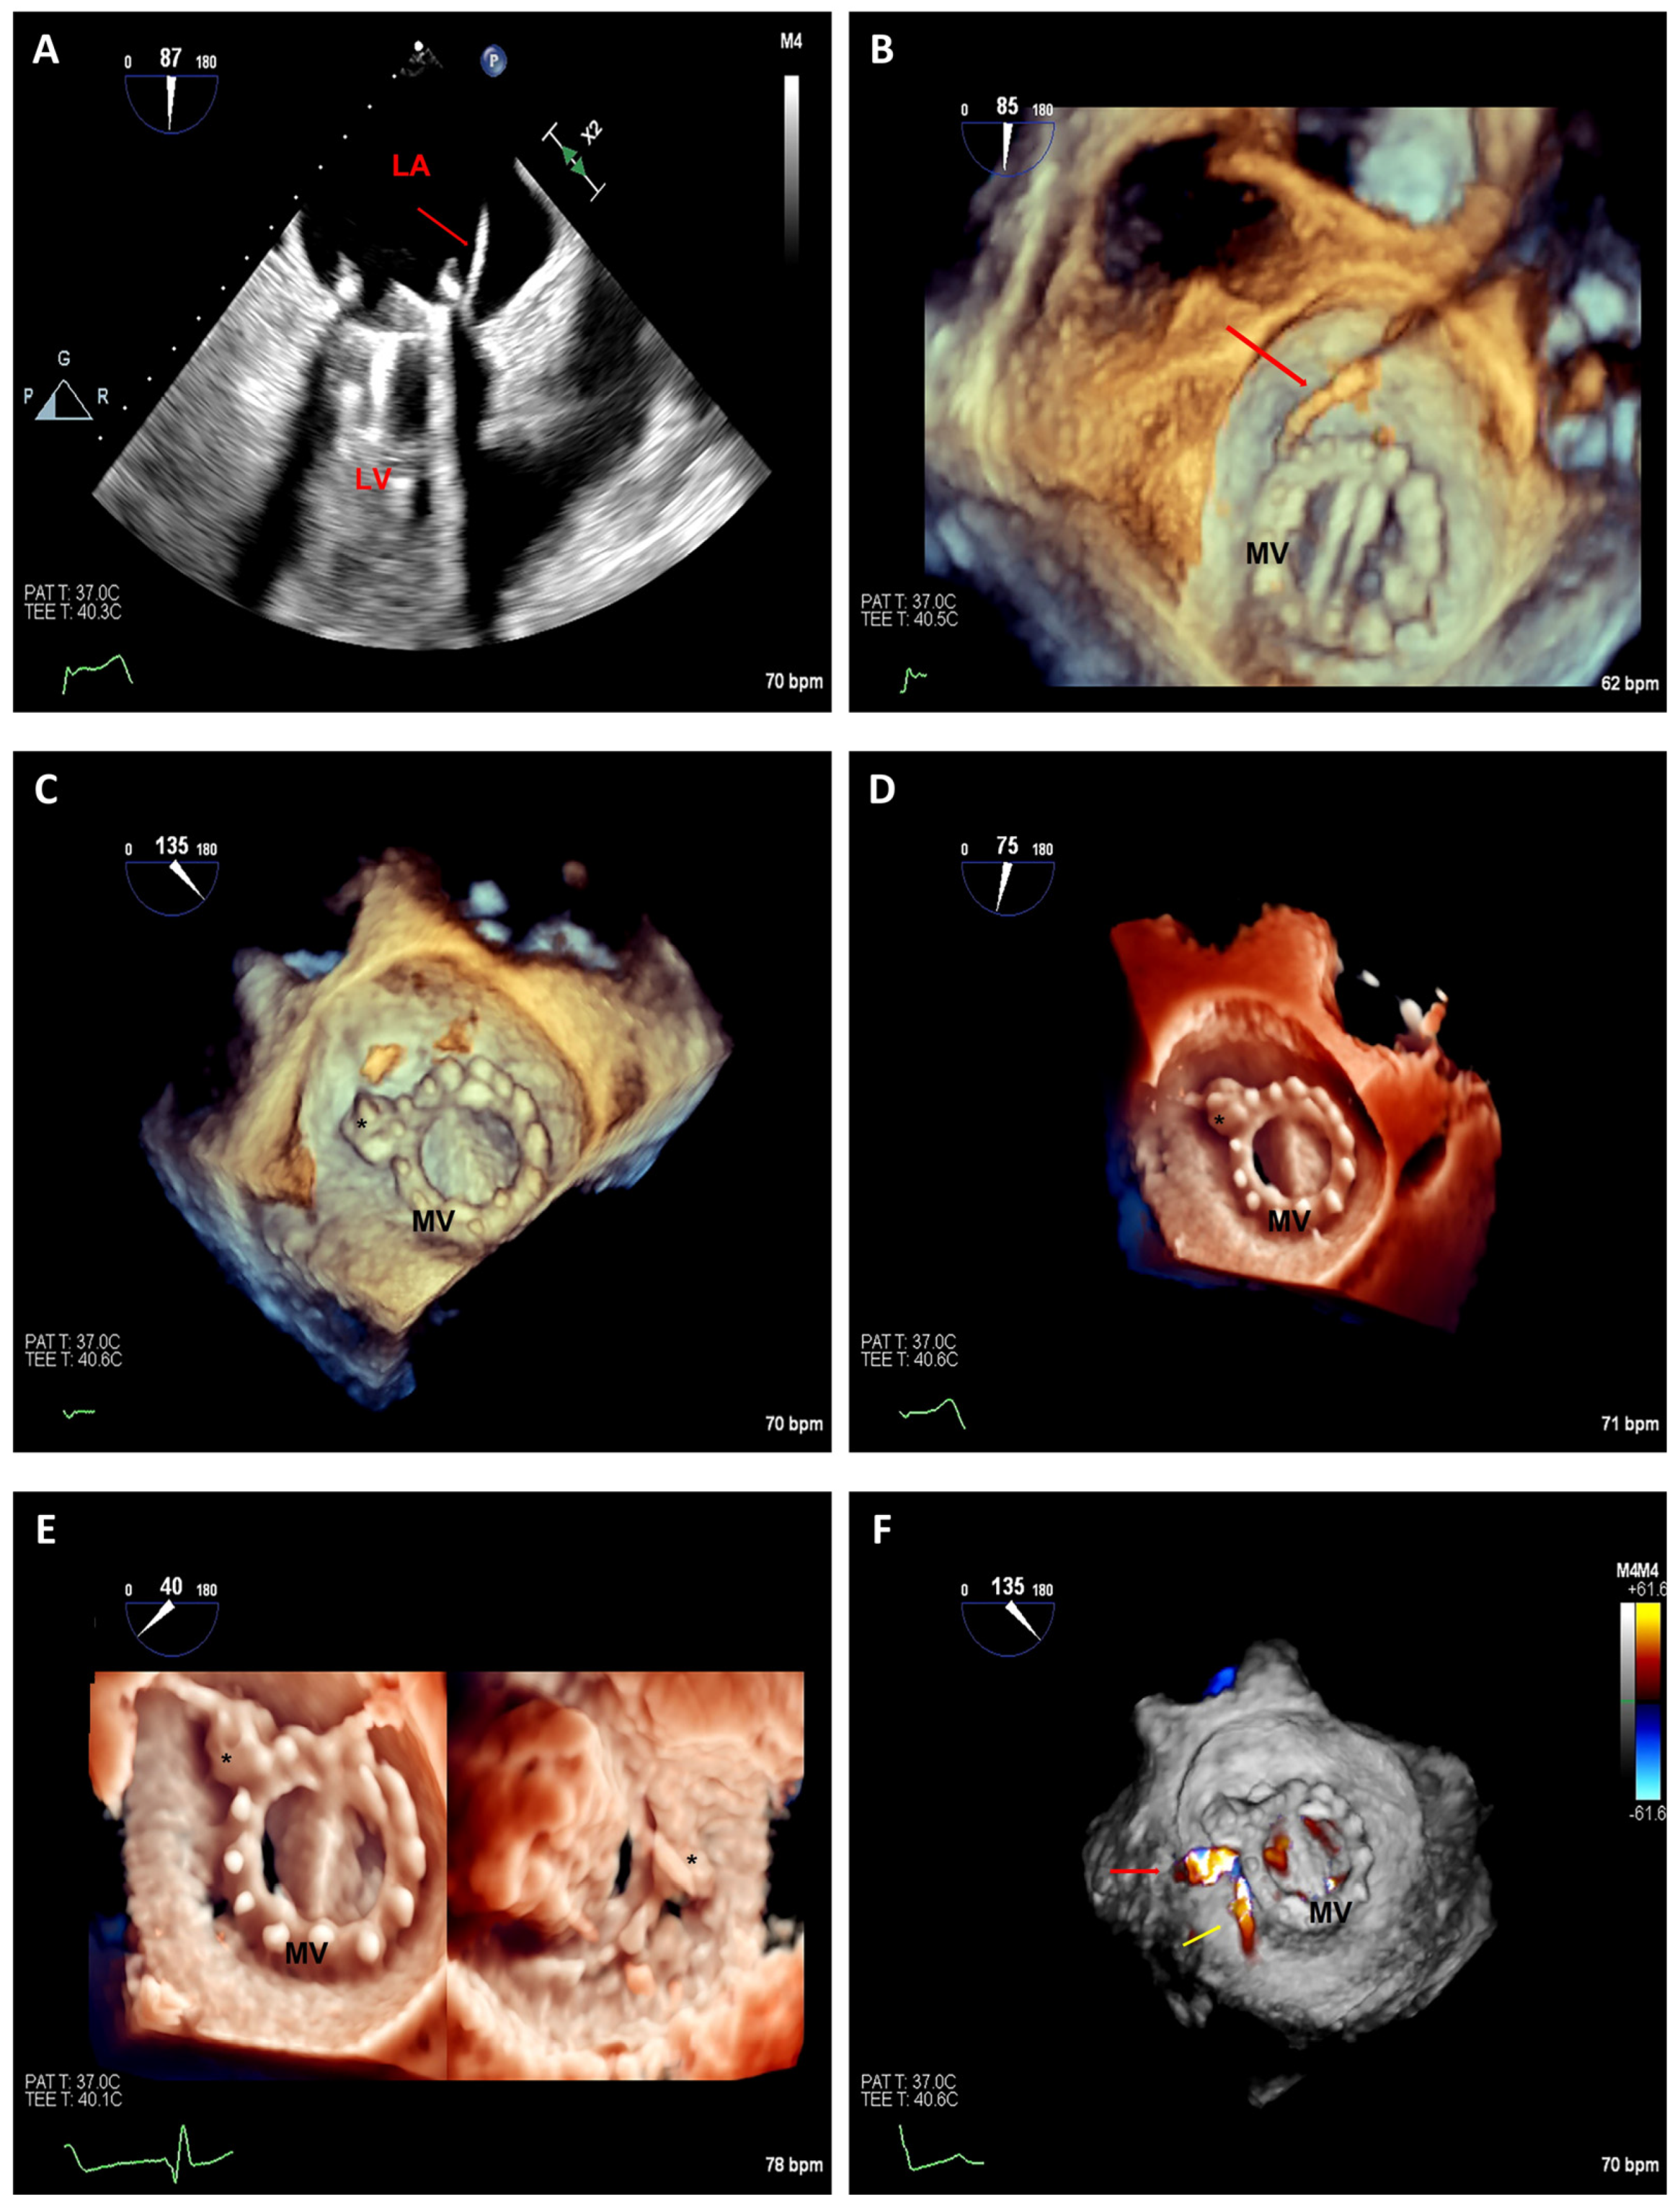

3.2.1. Edge-to-Edge Mitral Valve Repair